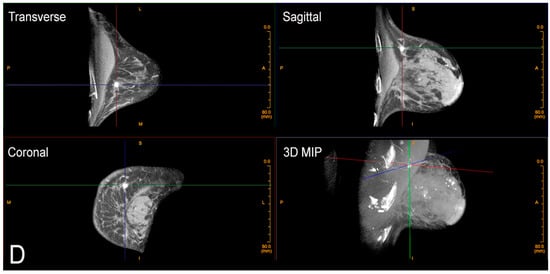

Figure 4.

Calcifications on CBBCT. Left CC (A) and MLO (B) views demonstrate pleomorphic micro-calcifications (arrow). (C) Unenhanced CBBCT images showing calcifications, which are marked with grid lines. (D) Contrast-enhanced CBBCT in the same patient showed an incidental mass marked with grid lines.